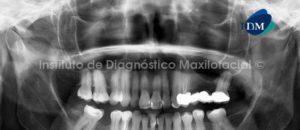

Paciente femenino de 42 años de edad es referida al Instituto de Diagnóstico Maxilofacial para la localización de un cuerpo extraño, tras un accidente en el procedimiento del bloqueo nervioso previo al tratamiento de conductos de la pieza 4.6.